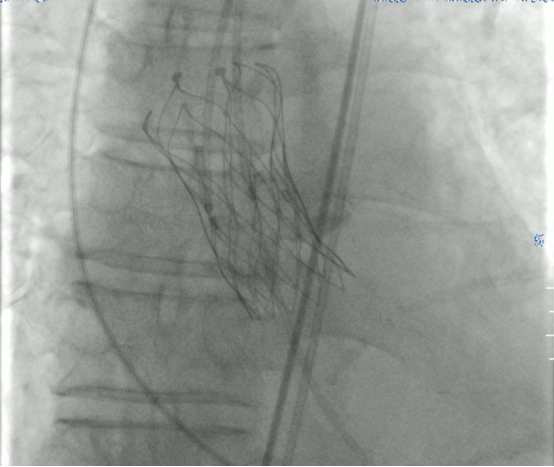

按照术前详细制定的手术方案,麻醉科、超声科、影像科“瓣膜团队”全力协作,8月15日手术如期进行,经股动脉顺利完成主动脉瓣置换手术,患者胸闷憋喘等情况明显改善,至此首例TAVR圆满成功。

什么是TAVR?经导管主动脉瓣置换术(TAVR)是通过股动脉送入介入导管,将人工心脏瓣膜输送至主动脉瓣区打开,从而完成人工瓣膜置入,恢复瓣膜功能。该技术具有创伤小、恢复快、安全性高,并发症少的优点,对于心功能衰竭的重度主动脉瓣狭窄患者,药物治疗效果差、外科开胸手术难以耐受,TAVR已成这类患者的“救命神招”!